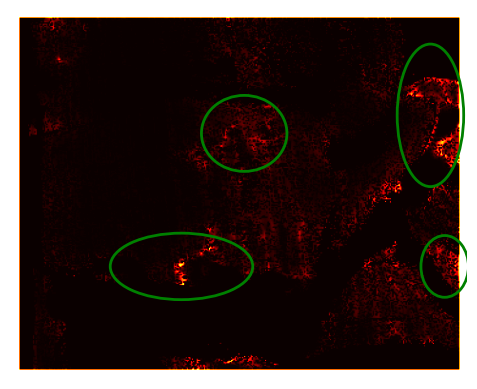

Uncertainty: As the network performs classification, it is easy to acquire the confidence in the predictions (Cao et al. 2018); the closer the Sigmoid output is to 0.5 the less confident the network is. An empirical assessment of the correlation between the disparity error and network confidence was made. It was concluded that there was a correlation between confidence and accuracy. An example of this is shown in Fig. 5. The ellipses highlight the same areas in each image. These results show a correlation between areas of high uncertainty and areas of low accuracy. Fig. 6 displays a histogram plot of the uncertainty and error in the above example. Each histogram bin represents the number of occurrences for each combination of uncertainty and disparity error. A positive correlation is seen between the disparity error and the uncertainty. This is numerical evidence of the correlation observed in Fig. 5. Analysing confidence is critical for healthcare application and the adoption of deep learning methods in clinical practice. This is an advantage for using structured light reconstruction, over disparity estimation, as this is naturally a classification task (where the classification is the final output).

Refer to caption

(a) Disparity error.

(b) Left uncertainty.

(c) Right uncertainty.

Figure 5: Disparity accuracy and uncertainty correlation. The brighter the pixel, the greater the uncertainty and the less accurate. The ellipses are drawn over the same pixels in all three images. Correlating high energy is observed in the areas within the ellipses.